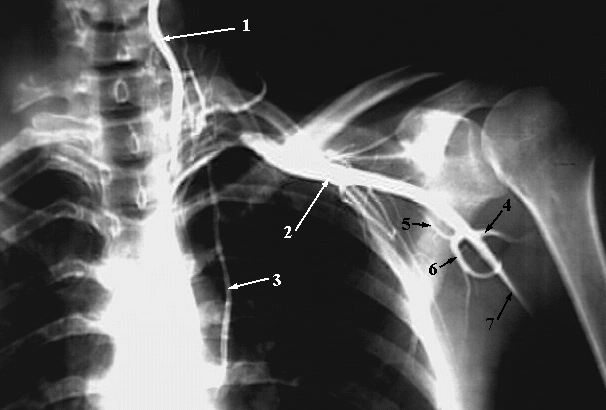

Upper Limbs: Axilla Angiogram:

1. Vertebral Artery

2. Axillary Artery

3. Internal Thoracic Artery

4. Posterior Humeral Circumflex Artery

5. Circumflex Scapular Artery

6. Subscapular Artery